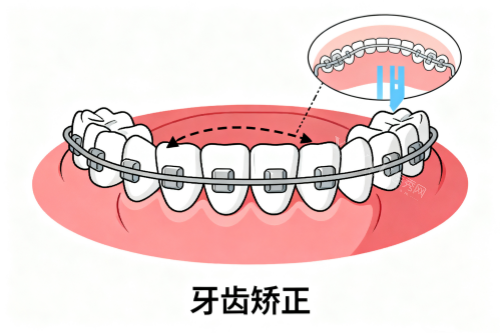

1. 智能化正畸:3D扫描预知结果,告别"盲人摸象"

"以前矫正牙齿得咬牙模,恶心得直干呕,现在用口扫仪5分钟就搞定!"在德嘉做隐形矫正的小刘,举着手机里的3D矫正方案激动地说,"医生直接把牙齿移动过程做成动画,连未来脸型变化都能看到!"

德嘉引进的智能化口扫仪,精度达0.02毫米,比传统取模误差减少80%。更出色的是,结合AI算法,能模拟出矫正后牙齿的咬合状态,连"笑线"弧度都能调整。这种"所见即所得"的技术,让年轻人直呼"黑科技救我狗命"。